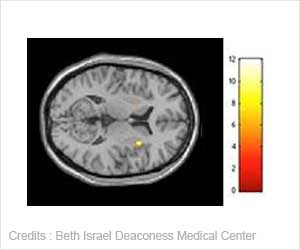

Periodontitis is a chronic inflammatory disease that destroys connective tissue and bone supporting the teeth. It has been associated with various systemic diseases, including diabetes and heart disease.Researchers from UB and Roswell Park Cancer Institute published the first study showing an association between long-standing periodontitis and risk of tongue cancer in the May 2007 issue of Archives of Otolaryngology - Head and Neck Surgery. Studies conducted elsewhere have found that HPV is an independent risk factor for a subset of head and neck cancers.

The study involved 30 patients newly diagnosed with squamous cell carcinoma on the base of the tongue between 1999 and 2005 at Roswell Park Cancer Institute for whom data was available on both periodontitis and tumor HPV status. Cumulative history of periodontitis was determined by assessing the loss of alveolar bone, the bones that underlie and support the teeth, via X-ray.

Results showed that 63 percent, or 19 out of 30 patients, had tumors that were positive for HPV-16 DNA; none of the tumor samples were found to contain HPV-18 DNA. In addition, 90 percent of patients with tumors positive for HPV had periodontitis, and 79 percent of patients whose tumors showed no presence of HPV did not have periodontitis.